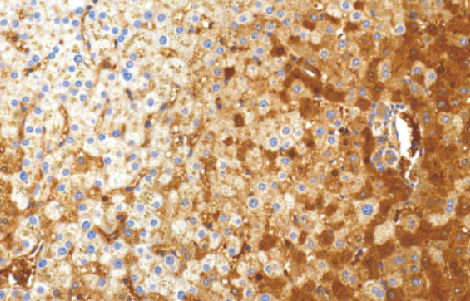

• Alpha-1Antitrypsin(AAT)兔抗人a-1-抗胰蛋白酶多克隆抗体

a-1- antitrypsin 在肝脏中合成,存在于血清和组织液中作为蛋白酶抑制因子,特别是具有弹性蛋白酶的抑制作用。主要作用表现为在炎症反应中中和中性粒细胞释放的弹性蛋白酶。a-1-antitrypsir缺乏可能导致肺等无法抑制弹性蛋白酶诱导的组织破坏。a-1antitrypsin 缺乏与全腺泡型肺气肿和肝病有关。在肝脏中,a-1antitrypsin 缺乏可能引发新生儿肝炎或者在少年期或成人期某些个体出现肝硬化。